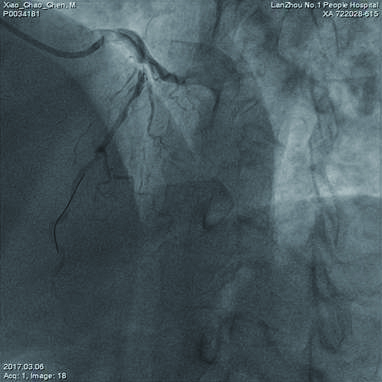

转入重症医学科后18:30行主动脉内球囊反搏,1:1反搏启动,正肾、副肾、多巴安及硝酸甘油微量泵辅助,因呼吸急促(35次/min),氧饱和度下降(80%),19:40呼吸机辅助呼吸。3月15日撤呼吸机,3月17日撤主动脉内囊反搏(IABP)。脱机后冠脉造影示:左前降支及左回旋支远端血流明显好转(图 3)。于3月24日行心脏不停跳冠状动脉搭桥术(OPCAB),左侧乳内动脉→左前降支(LIMA→LAD),升主动脉→大隐静脉→回旋支(AAO→SVG→CX)。术后11 d康复出院。

| 图 3 主动脉内球囊反搏11 d后左前降支血流明显好转 |